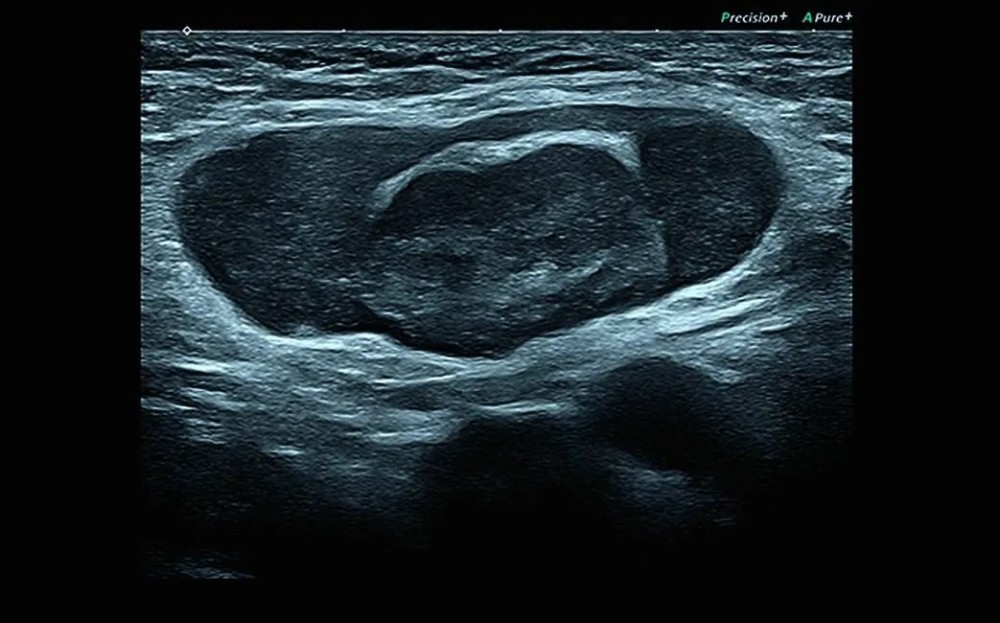

PLI-705BXLinear3.5 – 8.5Periferik damar, kiçik orqanlar, MSK

PLT-1204BTLinear7.5OB/GYN, MSK, həzm sistemi